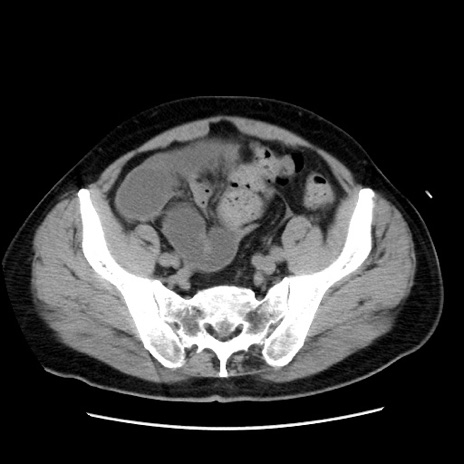

冠状断像

症例16(横断像)

【症例】 70歳代男性

【主訴】 腹痛、嘔吐

【現病歴】 約1ヶ月前より間欠的に腹痛と嘔吐あり、当院消化器内科を受診したところCTで多発する肝臓のLDAを指摘され、精査中であった。以降は消化器症状は安定していたが、2日前より嘔気と腹痛があり、同日より排便・排ガスが消失した。改善認めず、 本日、救急外来を受診した。

【既往歴】 大腸ポリープ切除後。

【身体所見】意識清明・会話良好、BT 36.3℃、BP 127/80mmHg、 P 80bpm、腹部:膨満あり、平坦・軟、上腹部正中および下腹部正中に圧痛あり、反跳痛なし、筋性防御なし。

【データ】WBC 7200、CRP 0.77